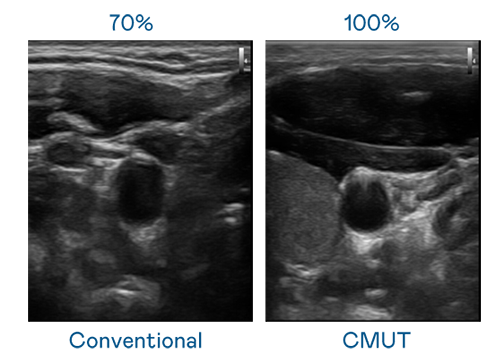

CMUT 技术是一种用电容式微机电元件来产生超音波讯号的技术。与传统 PZT 压电式技术相比,CMUT 频宽增加 30%,更宽频的超音波讯号让影像解析度大幅提升,是实现高影像品质医疗超音波扫描、促进精准医疗发展的关键技术。

大频宽带来超清晰影像

超音波影像的解析度高低,首先取决于探头能发出的讯号频宽。EVO CMUT 可提供高清晰的超音波讯号,提供高频宽、高灵敏度、影像纹理细节更高的超音波影像,协助医护人员缩短影像判读时间及利用精准的医疗影像进行诊断。